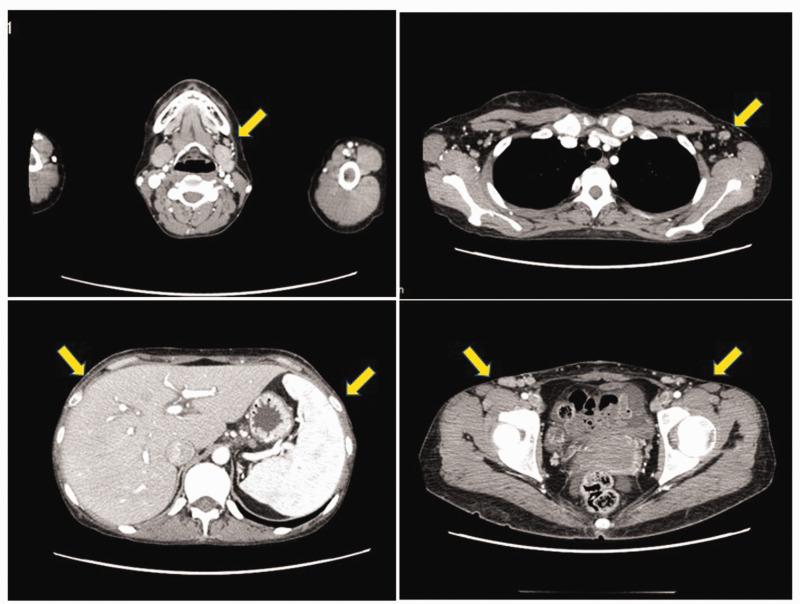

A 29-year-old woman with chronic, prolonged pustular psoriasis was admitted to our hospital because of high-grade fever and a systemic skin rash. General examination revealed a whole-body skin rash and superficial lymphadenopathy. Peripheral blood examination showed unclassified cells positive for CD3, CD4, and T-cell receptor αβ, and negative for CD20 and CD56. Soon after administration, she developed acute respiratory failure and required artificial ventilation. Bronchoalveolar lavage fluid showed increased numbers of eosinophils and abnormal lymphocytes of the same phenotype in peripheral blood and skin. She was diagnosed with eosinophilic pneumonia, and her respiratory failure was improved by corticosteroid therapy. Based on the histological findings of skin, lymph node, and bone marrow biopsies, a diagnosis of peripheral T-cell lymphoma not otherwise specified (PTCL-NOS), with positivity for CC chemokine receptor 4 was made. She received chemotherapy followed by allogeneic stem cell transplantation, which resulted in complete remission of her PTCL-NOS. She remained alive and disease-free 6 years later. This is the first reported case of PTCL-NOS developing during the clinical course of pustular psoriasis. The clinical manifestations of PTCL-NOS are complex, but an accurate diagnosis and appropriate therapy may produce a good clinical outcome in patients with PTCL-NOS.

一位 29 岁的女性患有慢性、迁延性脓疱性银屑病,因高热和全身性皮疹入住我院。全身检查发现全身皮疹和浅表淋巴结病。外周血检查显示未分类细胞 CD3、CD4 和 T 细胞受体 αβ 阳性,CD20 和 CD56 阴性。用药后不久,她出现急性呼吸衰竭,需要人工通气。支气管肺泡灌洗液显示外周血和皮肤中嗜酸性粒细胞和异常淋巴细胞数量增加,表型相同。她被诊断为嗜酸性粒细胞性肺炎,皮质类固醇治疗改善了她的呼吸衰竭。根据皮肤、淋巴结和骨髓活检的组织学发现,诊断为未分类的外周 T 细胞淋巴瘤(PTCL-NOS),CC 趋化因子受体 4 阳性。她接受了化疗和异基因造血干细胞移植,PTCL-NOS 完全缓解。6 年后,她仍然存活且无疾病。这是首例脓疱性银屑病病程中发生 PTCL-NOS 的报道。PTCL-NOS 的临床表现复杂,但准确的诊断和适当的治疗可能会给 PTCL-NOS 患者带来良好的临床结局。